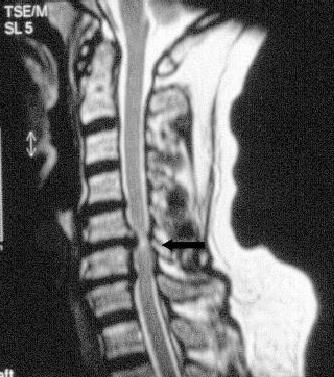

Die Spinalkanalstenose ist in den meisten Fällen Ausdruck einer degenerativen Erkrankung. Durch den Bandscheibenverschleiß kommt es zu einer minimalen Lockerung und Überbeweglichkeit der Wirbel. Bereits durch einen Wirbelversatz kann ein von 2 Wirbeln gebildeter Kanal verkleinert werden. Der Körper versucht der Lockerung entgegenzuwirken und vergrößert Bänder und Knochen (Gelenke). Auch dadurch wird der Nervenkanal eng. Besonders an der Halswirbelsäule versucht der Körper sogar Knochenbrücken, sog. Osteophyten, zu bilden, die Nervengewebe einengen.

Nicht zuletzt können auch Bandscheibenvorwölbungen oder Vorfälle zu einer Spinalkanalstenose führen.

Halswirbelsäule

Zumeist ist eine Kernspintomographie ausreichend. Bei Verdacht auf Rückenmarksschaden ist zusätzlich eine elektrophysiologische Untersuchung der Nervenleitung erforderlich.